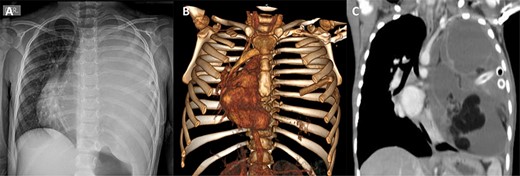

(A) Resection of the mediastinal mass via a median sternotomy associated to left anterior thoracotomy. (B) Entry into the pleural space was performed through the sixth intercostal space. (C) Many adhesions to thoracic wall and diaphragm were found. (D) Phrenic nerve presented adhesions to the tumor. Also, it had founded a nutritional artery depending on left internal mammary artery. (E) Section of the left internal mammary vessels, dissection of the phrenic nerve, ligation of the nutritional vessel, mediastinal tumor excision, ligation of the thymic vessels and thymectomy was performed. (F) The mediastinal tumor, excised in block, was red–gray colored, well circumscribed and capsuled with a size of 15 × 15 × 20 cm

The patient underwent a total resection of the mediastinal mass via a median sternotomy. Given the extension of the teratoma and adhesions to the chest wall, an additional approach with a left anterior thoracotomy was made (Fig. 2). Entry into the pleural space was performed through the sixth intercostal space to obtain safe visualization of the cavity and proceed to tumor excision. Many adhesions were found to the thoracic wall, diaphragm and phrenic nerve. Additionally, a nutritional artery depending on left internal mammary artery was discovered with collateral veins draining to brachiocephalic vein. A section of the left internal mammary vessels, dissection of the phrenic nerve, ligation of the nutritional vessel, mediastinal tumor excision, ligation of the thymic vessels and thymectomy was performed. Thoracic drainage tubes (two) were placed. The mediastinal tumor, excised in block, was red–gray colored, well circumscribed and capsuled with a size of 15 × 15 × 20 cm. Postoperatively, the collapsed left lung was re-expanded, and the patient was extubated on Day 1 (Fig. 3). The patient recovered from the operation and was discharged on the ninth postoperative day. Preoperative atelectasis of the left lung partially resolved, and the pathological examination revealed a benign mature teratoma with cystic degeneration. Anatomical pathology test showed the presence of glandular epithelial cells concomitant with the presence of cartilage tissue (Fig. 4) The histochemistry test revealed CD3(+) CD20(+) TDT(−) CD5(−) cells. Thymic tissue was negative for malignancy; nine lymph nodes showed reactive follicular hyperplasia.